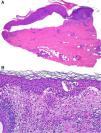

HistopatologíaSe realizaron 2 biopsias cutáneas, la primera reveló una ampolla subepidérmica con escaso contenido inflamatorio (fig. 2A), y la segunda evidenció una intensa espongiosis eosinofílica (fig. 2B).

Diagnóstico diferencialEl diagnostico diferencial ante la presencia de lesiones ampollosas durante el postoperatorio incluye el impétigo ampolloso, que se descartó ante un cultivo negativo y un eccema alérgico de contacto, que se descartó tras la realización de las pruebas epicutáneas. Ante un estudio histológico de ampolla subepidérmica con escaso contenido inflamatorio hay que incluir la variante «cell-poor» de penfigoide ampolloso, la epidermólisis ampollosa, la porfiria cutánea tarda, quemaduras (p. ej., por crioterapia) e incluso la necrólisis epidérmica tóxica1. El cuadro clínico junto a una segunda biopsia que mostraba un patrón de espongiosis intensamente eosinofílica nos llevó al diagnóstico de penfigoide ampolloso localizado2, que se confirmó tras la detección de anticuerpos antimembrana basal en el suero de nuestro paciente.